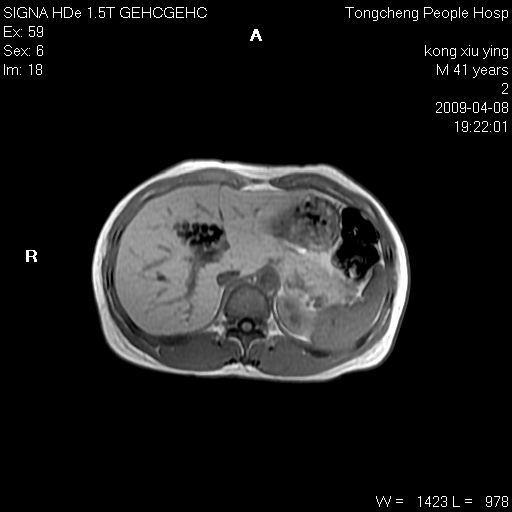

标题: CL1008:【经典】胆囊石榴籽样结石。

女,41岁。健康体检——彩超提示:胆囊显示不清。平素健康,无不适感。

腹部mr扫描及mrcp,图像如下:

标题: 胆囊阴性结石ct图片

好啊!我有ct的插进来啊,楼主请允许噶。